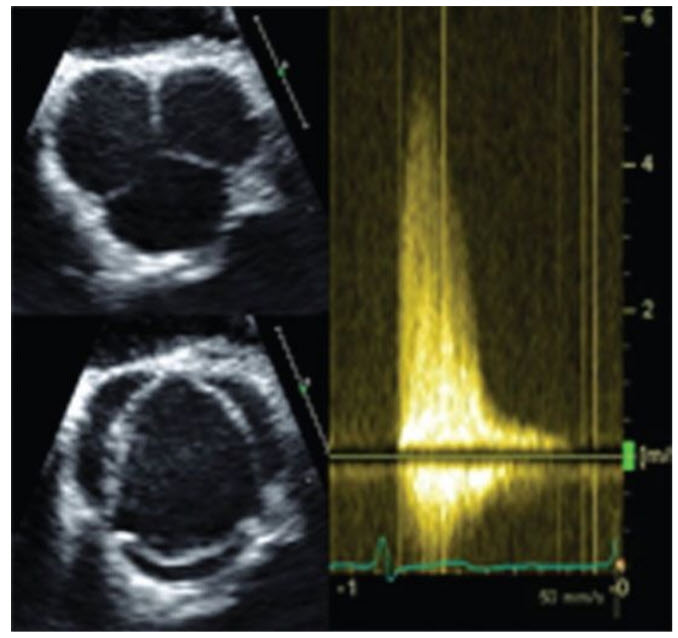

A 26-year-old woman with a history of hypertrophic obstructive cardiomyopathy is referred for consideration for septal myectomy. She has NYHA class III dyspnea on exertion despite maximal medical therapy. On echocardiography, there is severe asymmetric septal hypertrophy with severe systolic anterior motion of the mitral valve. There is a late-peaking gradient across the LVOT of 60 mmHg, which increased to 105 mmHg with Valsalva. She has a structurally normal mitral valve on cardiac MRI with moderately severe posteriorly directed MR (Fig. below).

What would you advise her regarding surgery?

She will probably not need surgery on her mitral valve. MR secondary to systolic anterior motion of the mitral valve is related to hydrodynamic drag and Venturi effects on the anterior mitral valve. Often there are intrinsic mitral valve abnormalities that, in combination with septal hypertrophy, predispose to systolic anterior motion. Abnormal chordal attachments or hypermobile papillary muscles seen best on cardiac MRI may mandate chordae remodeling or papillary muscle reorientation; however, in this case the mitral valve apparatus is noted to be structurally normal. Relief of the hydrodynamic effects of a narrowed LVOT after myectomy will usually result in significant improvement in MR without further surgery. Before chest closure, careful assessment of MR should be done after the myectomy, usually with isoproterenol infusion, to ensure resolution.